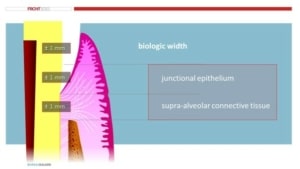

Negatieve gevolgen van bruxisme

Parodontale problemen kunnen een negatief gevolg zijn van bruxisme. Volgens de literatuur is er geen bewijs dat traumatische occlusale krachten leiden tot parodontaal aanhechtingsverlies, niet-carieuze cervicale laesies of tandvleesrecessies. Verder leiden traumatische occlusale krachten tot adaptieve mobiliteit bij tanden met normale ondersteuning, terwijl ze leiden tot progressieve mobiliteit bij tanden met verminderde ondersteuning, waarvoor meestal spalken nodig is.